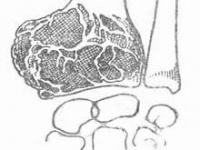

多见于年轻成人。肿瘤主要由巨细胞(破骨细胞)和基质细胞构成。骨巨细胞瘤在我国是较常见的原发性骨肿瘤之一,此瘤生长活跃,对骨质侵蚀破坏性大,如得不到及时妥善的治疗,可造成严重残废而导致截肢,少数病例尚可转移而致命。按良性和恶性程度分为三度。症状:邻近关节的肿瘤,生长缓慢,局部可有肿胀,疼痛及压痛,关节活动度常受限,瘤内出血或病理骨折往往伴有严重疼痛。检查:X线片表现:骨骺处有局限的囊性改变,一般呈溶骨性破坏,也可有“肥皂泡”样改变,其扩展一般为软骨所限。不破入关节,少有骨膜反应,肿瘤范围清楚,初发时病变在骨骺内旁侧,发展后可占骨端的全部,骨皮质膨胀变薄,有的可以穿破,进入软组织。X线片可显示其一般特点,但仍不足以确诊。

X线主要表现为骨端变心位溶骨性破坏而无滑膜反应,病灶骨皮质膨胀变薄,呈肥皂泡样改变。

X线片表现:骨骺处有局限的囊性改变,一般呈溶骨性破坏,也可有“肥皂泡”样改变,其扩展一般为软骨所限。不破入关节,少有骨膜反应,肿瘤范围清楚,初发时病变在骨骺内旁侧,发展后可占骨端的全部,骨皮质膨胀变薄,有的可以穿破,进入软组织。X线片可显示其一般特点,但仍不足以确诊。